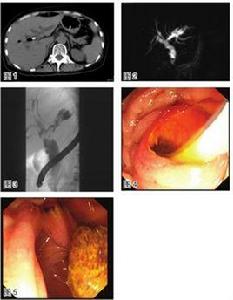

超聲檢查

B超為診斷膽囊息肉樣病樣病變的首選方法,具有無創、簡便、經濟和病變檢出率高和易普及等優點。膽囊息肉樣病樣病變的共同特點是向膽囊腔內隆起的回聲光團,與膽囊壁相連,不伴有聲影,不隨體位改變而移動。膽固醇息肉常為多發,息肉樣,有蒂,常小於10mm,蒂長者可在膽囊內擺動,高輝度不均一的回聲光團,無聲影,不隨體位變動而移位。炎性息肉呈結節狀或乳頭狀,多無蒂,直徑常小於10mm,最大可達30mm,有蒂或無蒂,呈低輝度回聲、無聲影。腺肌瘤樣增生B超下可見突入肥厚膽囊壁內的小圓形囊泡影像和散在的回聲光點。超聲檢查的誤診率或漏診率受膽囊內結石的影響,往往是發現了結石,遺漏了病變。也有因病變太小而未被發現者。

超聲內鏡檢查(EUS)可清楚地顯示出膽囊壁的3層結構,從內向外顯示,回聲稍高的黏膜和黏膜下層,低回聲的肌纖維層和高回聲的漿膜下層和漿膜層。在膽固醇息肉、腺瘤及膽囊癌的鑑別診斷方面有重要作用,對於B超難以確診的病例,用EUS檢查有效。膽固醇息肉為高回聲光點組成的聚集像或多粒子狀結構,膽囊壁3層結構清楚。膽囊癌為乳頭狀明顯低回聲團塊,膽囊壁的層次破壞或消失,並可了解腫瘤浸潤的深度。此法對膽囊壁息肉樣病變的顯像效果明顯優於普通B超檢查,但對於膽囊底部病變的檢查效果較差。

X線膽囊造影

包括口服膽囊造影、靜脈膽道造影及內鏡逆行性膽道造影等,是一項有用的診斷方法。影像特點主要為大小不等充盈缺損。但是大多數報導認為膽囊造影的檢出率和診斷符合率偏低,一般約為50%(27.3%~53%)。檢出率低受膽囊功能不良、病變過小或膽囊內結石等因素的影響。

CT檢查

膽囊息肉樣病樣病變的CT檢出率低於B超,高於膽囊造影,檢出率為40%~80%不等。其影像學特點與B超顯像相似。如果在膽囊造影條件下行CT檢查,顯像更為清楚。